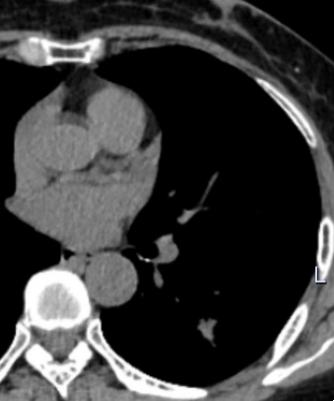

7月22日林女士遵照刘先领教授医嘱复查肺部CT,神奇的一幕出现了,其原左下肺“恶性肿瘤”完全消失,林女士免除了一次全麻大手术带来的风险,节省了高达数万元的医疗费用,更重要的是保住了计划切除的重要脏器(肺叶),全家人喜极而泣。

2023年7月20日(抗炎治疗后结节消失)